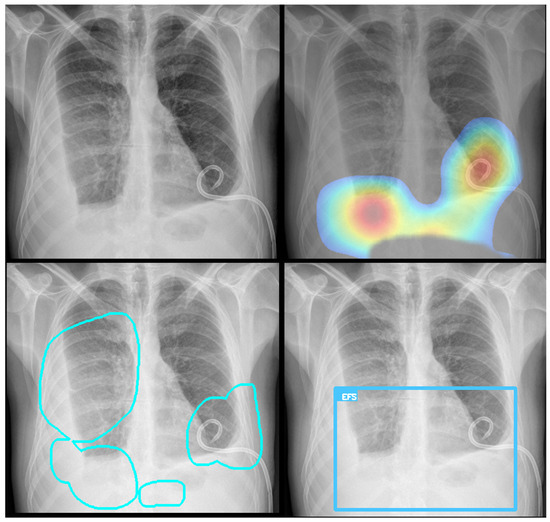

Before training, radiologists reviewed and verified the images, applying annotations using a proprietary software application (Figure 1). The dataset exhibited a significant class imbalance, reflecting the real-world prevalence of the pathology. For training binary classifiers, studies with definitive labels (1.0 for present, 0.0 for absent) were used. In contrast, studies with missing labels for a specific finding were excluded from the loss calculation for that task. Table 2 shows the distribution for a selection of key labels. The list of pathologies was selected based on the availability of labeled data, balanced with clinical importance for the ED. The ‘normal’ and ‘abnormal’ pools included cases with pathologies beyond the specifically targeted list; these were categorized under the general “yesfinding” class.

Figure 1. All labeled images were proofed by a radiologist who manually drew a region of interest around the pathology and assigned a finding, as shown here for an alveolar opacity circled by the dashed line.